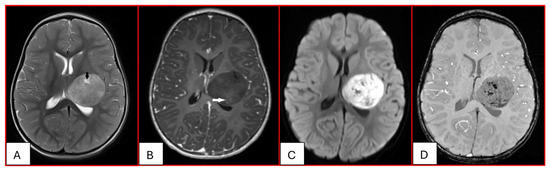

Since their first description by Rorke in 1995, the histogenesis of ATRTs has remained an enigma. Due to the expression of neural, epithelial, and mesenchymal markers, they likely derive from pluripotent fetal cells. Based on genetic and DNA methylation status and transcriptome profiles, ATRTs are further divided into three distinct molecular subgroups: ATRT-SHH, ATRT-TYR, and ATRT-MYC; further subclassifications have also been proposed. The WHO Classification of CNS tumors has included ATRTs in “Embryonal Tumors”. ATRTs are distinct from other embryonal tumors in their clinical presentation, tumor location, imaging characteristics, and prognosis. ATRTs often represent a surgical challenge as treatment requires removing a deep-seated large vascular mass from young patients. They are often resistant to conventional chemotherapy. Radiation therapy, which is imperative, raises serious concerns with regard to effects on the developing CNS of young patients. Safe and effective therapeutic measures are urgently needed.